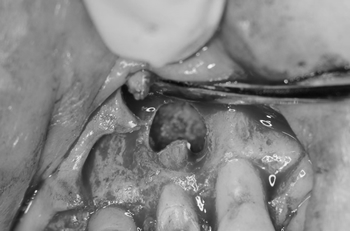

根の先は根管が枝別れしていて、感染セメント質が認められるので、3mm根をカットします。(3mmルール)

病巣はかなり大きくかったですが、徹底的に除去しました。

切断した、根断面をマイクロミラーで精査し、原因を究明します。 その後超音波ダイヤモンドチップで逆根管充填窩洞を形成しているところです。

MTAセメントで逆根管充填します。MTAは非常に扱いにくい材料ですので特殊なキャリア、コンデンサーを使用します。